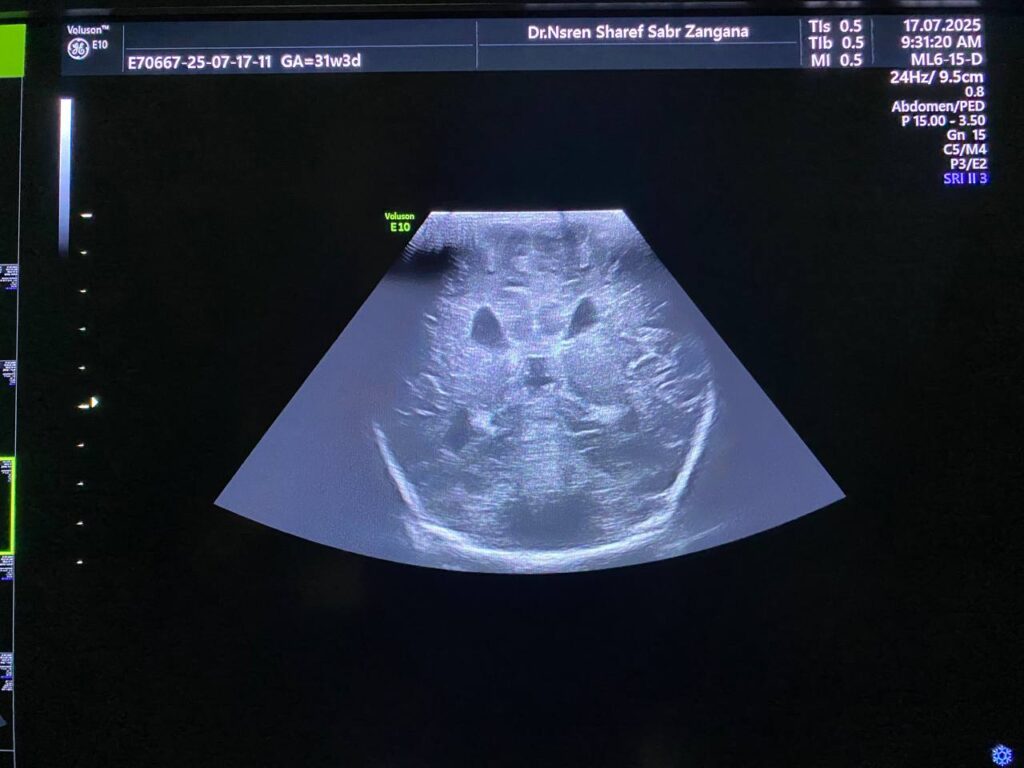

Mild hydrocephaly , maximum diamter of the posterior atrium of the lateral ventricles 16mm

Also mild dilated Third ventricle diamter 4.7mm , no dilated 4th ventricle seen , mostly due to mild stenosis at Sylvuis aqueduct